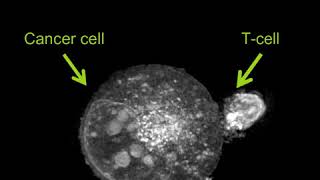

Can you kill a tumor cell? Label-free Live Cell Imaging: Activated T-Cell Killing Cancer Cell

Label-free Live Cell Imaging: Activated T-Cell Killing Cancer Cell

Can you kill a tumor cell? Label-free Live Cell Imaging: Activated T-Cell Killing Cancer Cell

Label-free Live Cell Imaging: Activated T-Cell Killing Cancer Cell